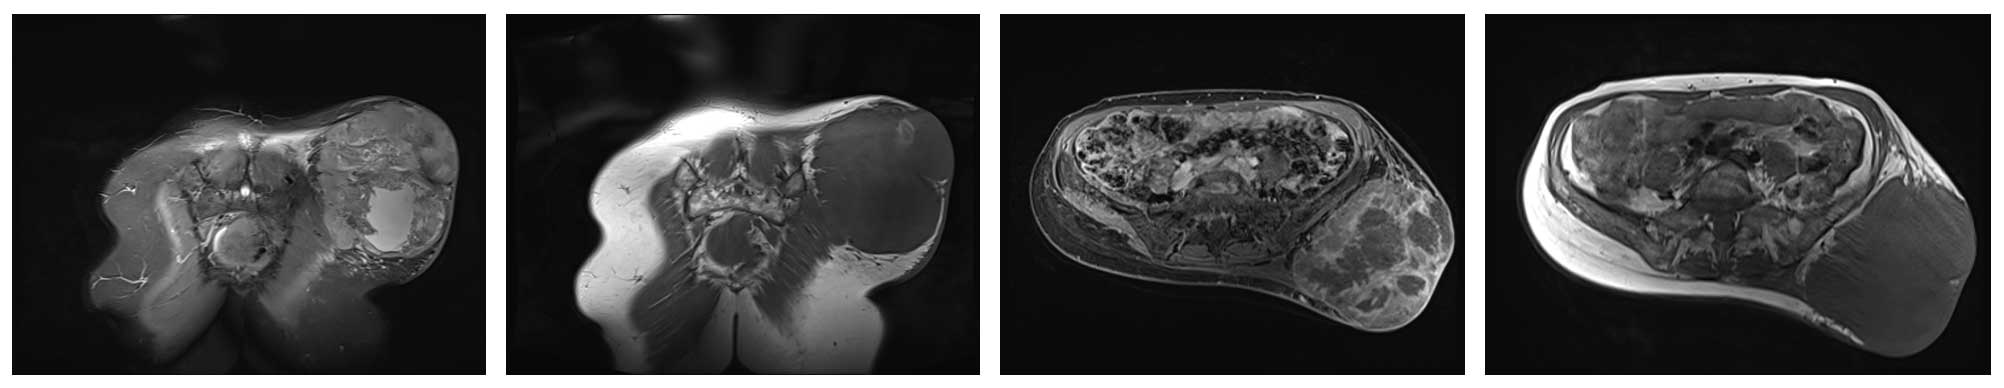

Ameliyat Öncesi: MR’da sağ gluteal bölgede düzensiz sınırlı heterojen büyük boyutlu tümör dokusu görülmekte.